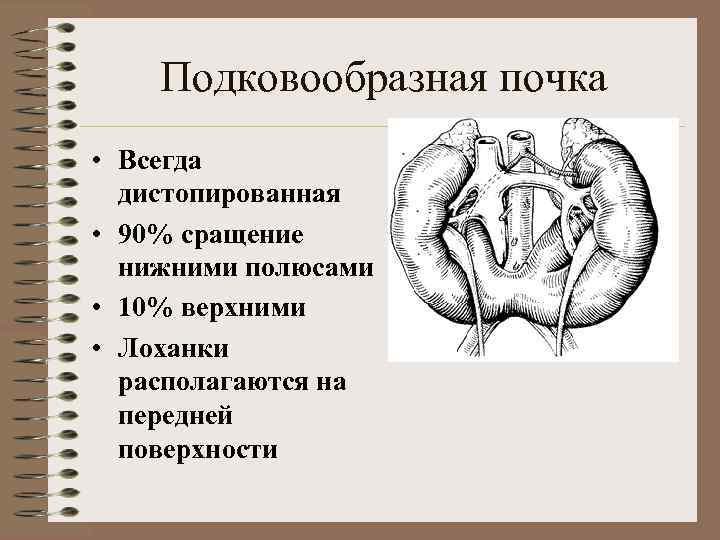

Подковообразная почка • Всегда дистопированная • 90% сращение нижними полюсами • 10% верхними • Лоханки располагаются на передней поверхности